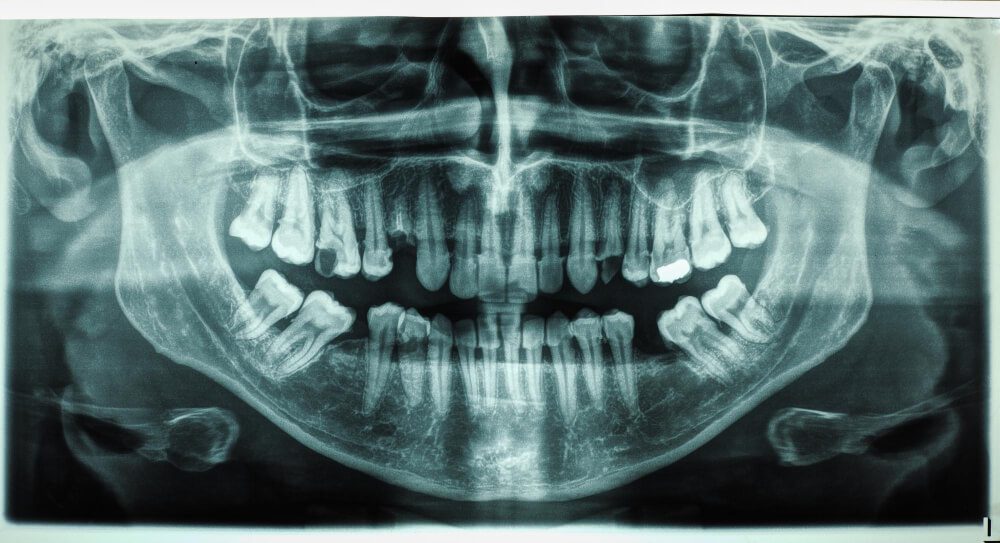

الأشعة البانورامية والأشعة المقطعية: دليل المزايا والاستخدامات ودورها في نجاح زراعة وتقويم وجراحة الأسنان (د. محمد عمارة).

الأشعة البانورامية والمقطعية: الدليل الشامل للتصوير ثلاثي الأبعاد والتشخيص الدقيق في طب الأسنان البند 1: المقدمة: أهمية التصوير الإشعاعي المتقدم في طب الأسنان تُعد صحة الفم والأسنان جزءاً أساسياً من الصحة العامة، ولا يمكن تحقيق خطة علاجية ناجحة ودائمة دون الاعتماد على التشخيص الدقيق. فما تراه العين المجردة ليس كافياً؛ إذ تكمن معظم المشكلات الجذرية